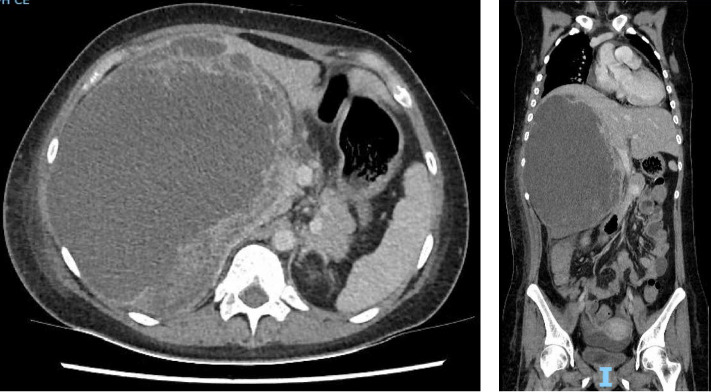

A liver abscess can be due to several different microbiological aetiologies. While pyogenic liver abscess is most frequently encountered, amoebic liver abscess and hydatid cyst caused by the parasites, Entamoeba histolytica and Echinococcus granulosus, respectively, should be considered whenever there is epidemiological exposure. As parasitic infections are now rarely seen in clinical practice in developed countries with improvement in sanitation, lack of clinical experience in managing amoebic liver abscesses and overlapping clinical and imaging features between amoebic and pyogenic liver abscesses may lead to delay in diagnosis. In particular, although amoebic liver abscesses respond well to treatment if diagnosed early, they can progress and rupture with high mortality if treatment is delayed. Hence, early diagnosis and prompt initiation of antimicrobials are crucial to prevent complications and death. This case report highlights a case of a very large 21 cm ALA in a young lady to illustrate the challenges faced during diagnostic evaluation.

Abstract Image